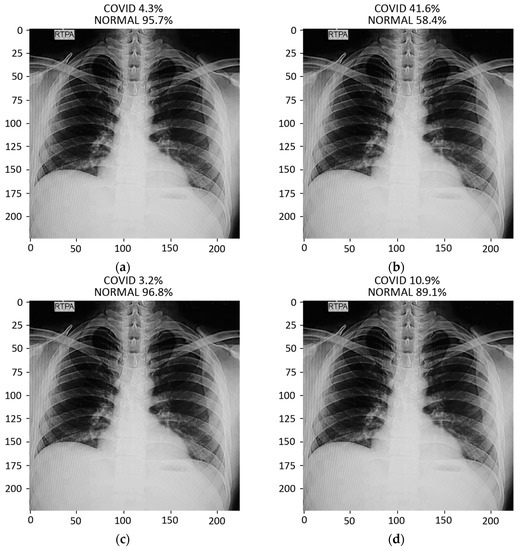

The prediction result for a chest X-ray of a local COVID-19-positive patient for each model is given in Figure 13a–d. The DenseNet-121 had the highest probability percentage of COVID-19, i.e., 99.9%. In order to highlight the area where the model is paying the most attention during feature extraction, the Grad-CAM technique was applied. The Grad-CAM results of all four models under study are given in Figure 14. Moreover, the results of the predicted normal patients for each model are shown in Figure 15a–d. Considering these results, the MobileNet has the highest probability of 96.8% for the prediction of a normal chest X-ray.

Figure 13.

Results of prediction on a verified local Pakistani COVID-19 chest X-ray: (a) DenseNet-121; (b) VGG16; (c) MobileNet; (d) ResNet-50.